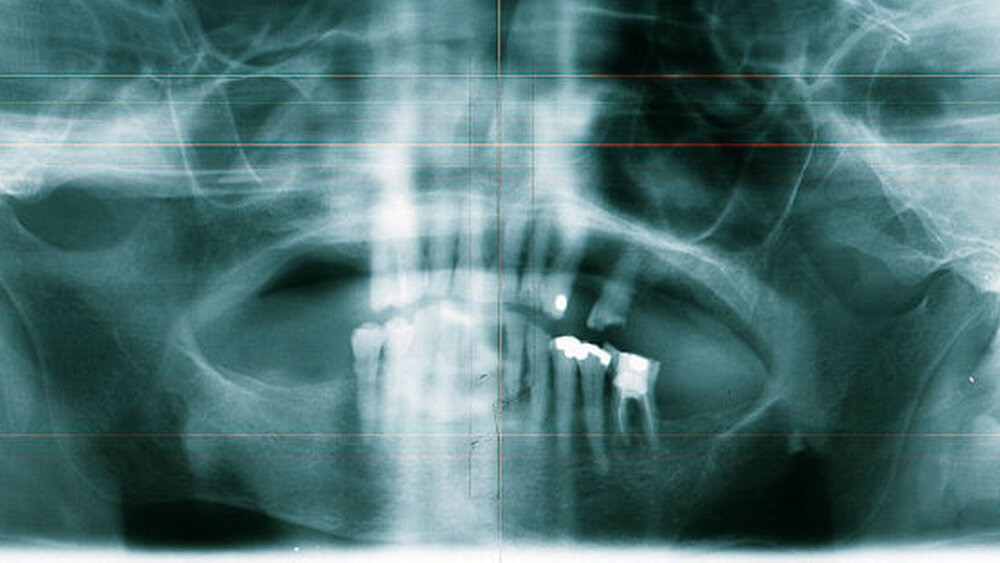

In der alio loco angefertigten Panoramaschichtaufnahme (Abbildung 2) stellte sich in regio 27 ein an eine Extraktionsalveole erinnernder Knochendefekt dar. Die Patientin konnte sich aber nicht mehr erinnern, wann sie den Zahn verloren hatte. Nebenbefundlich zeigte sich neben einem parodontal geschädigten Restgebiss ein apikal beherdeter Zahn 36. Eine Therapie lehnte die Patientin allerdings ab.